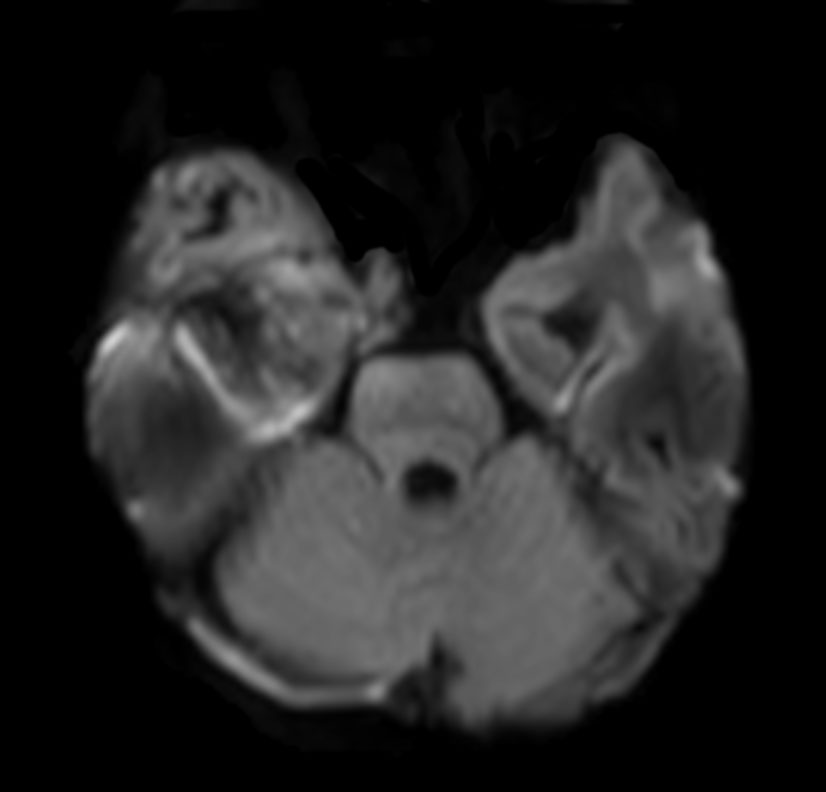

Axial DWI (b1000)

-